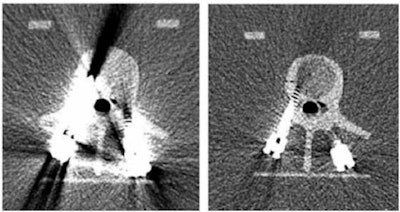

- Reduced beam hardening and metal artifacts

The reduction of radiation dose is particularly promising with applications such as lung cancer screening, McCollough said, citing a study that showed that photon-counting detector CT offered better Hounsfield unit (HU) stability at lower dose settings with better reproducibility than EID. McCollough also shared images that show the difference between conventional CT and photon-counting CT across a variety of applications.